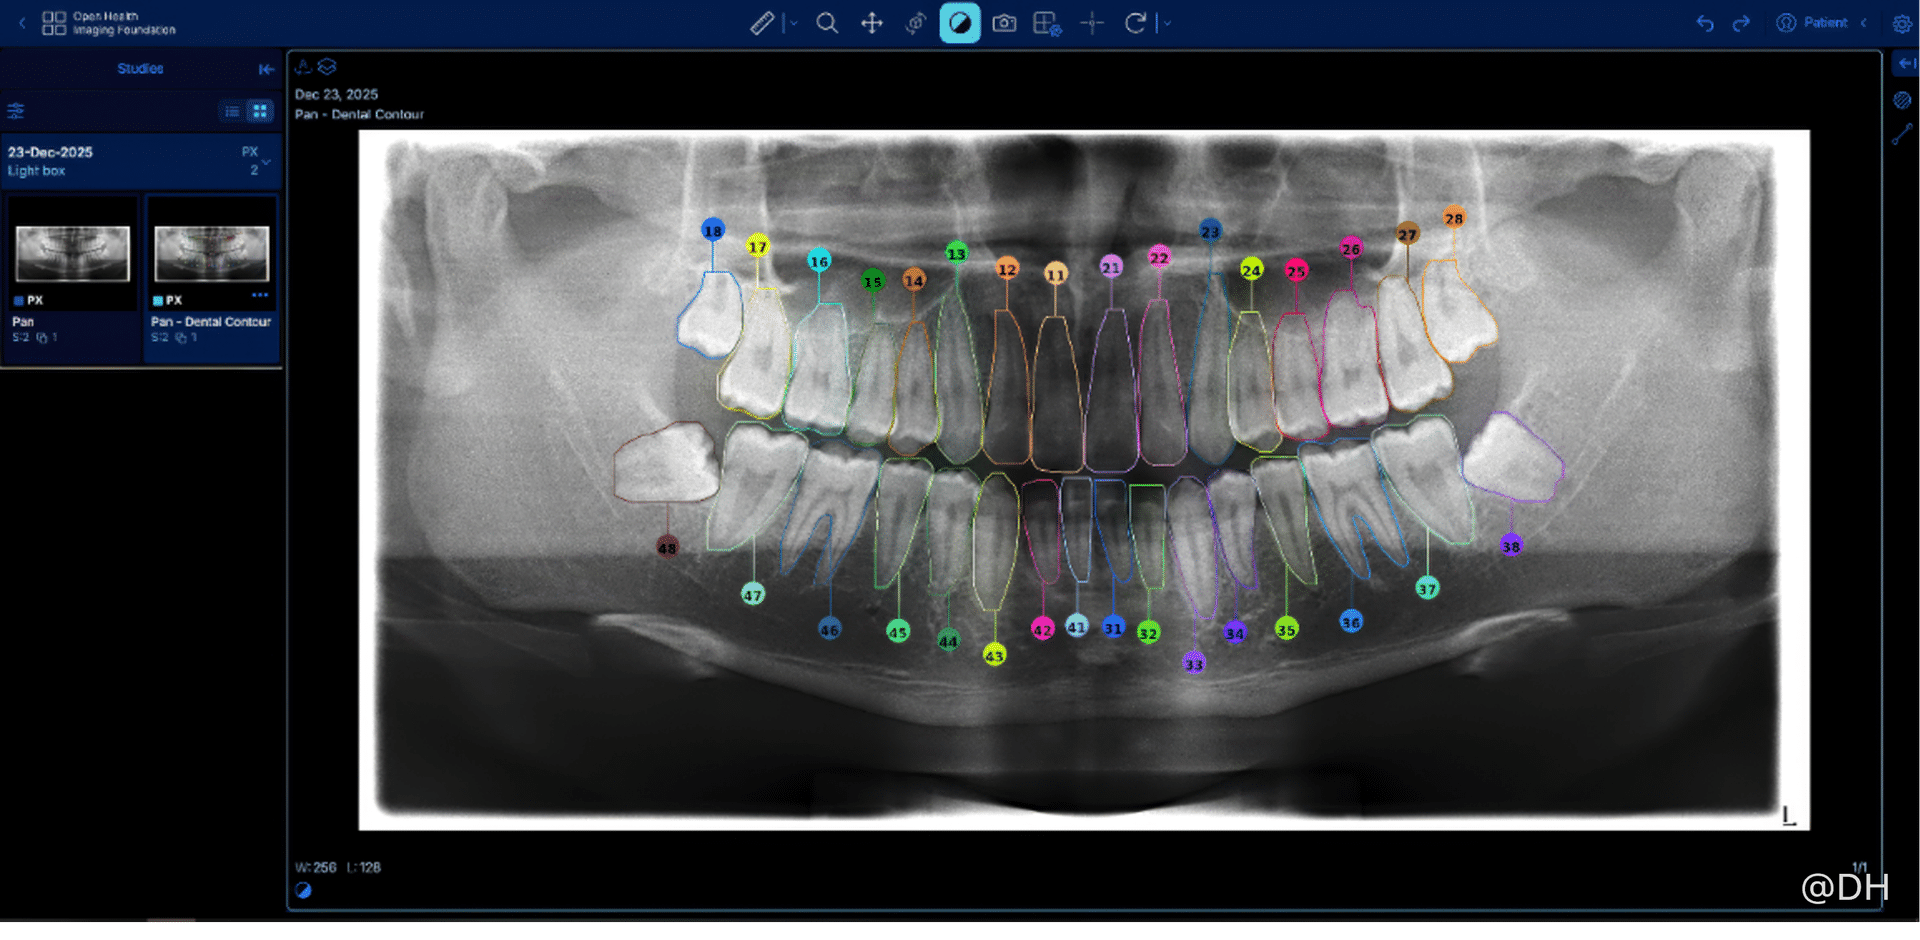

图片说明﹕同一幅 X光影像,经 AI 分析后,已检测出牙齿、分割牙齿并分配了 FDI 牙齿编号。

卫生署已采用电子临床资讯管理系统多年,但工作流程上仍依靠人手输入病人的临床牙齿检查资料,每个个案平均需时10分钟。为减轻牙医与助理的临床文书负担,优化服务流程,卫生署去年开展名为“人工智能辅助牙科图表及解读X光影像系统”的概念验证项目。项目利用先进的半监督对比学习方法,以AI解读牙科X光影像,AI先自动侦测并分割牙齿影像,根据空间与形态特征为每伙牙齿标注国际牙科联盟(FDI)牙齿编号;项目同时验证了将影像分析转化为结构化资料,自动生成牙科图表,并与临床管理系统整合的潜力。

为期约六个月的概念验证项目已于今年一月成功完成,项目所发展出的解读牙科X光影像的AI原型,临床案例灵敏度高达96%,牙齿级精确度高达94%,效果令人满意。